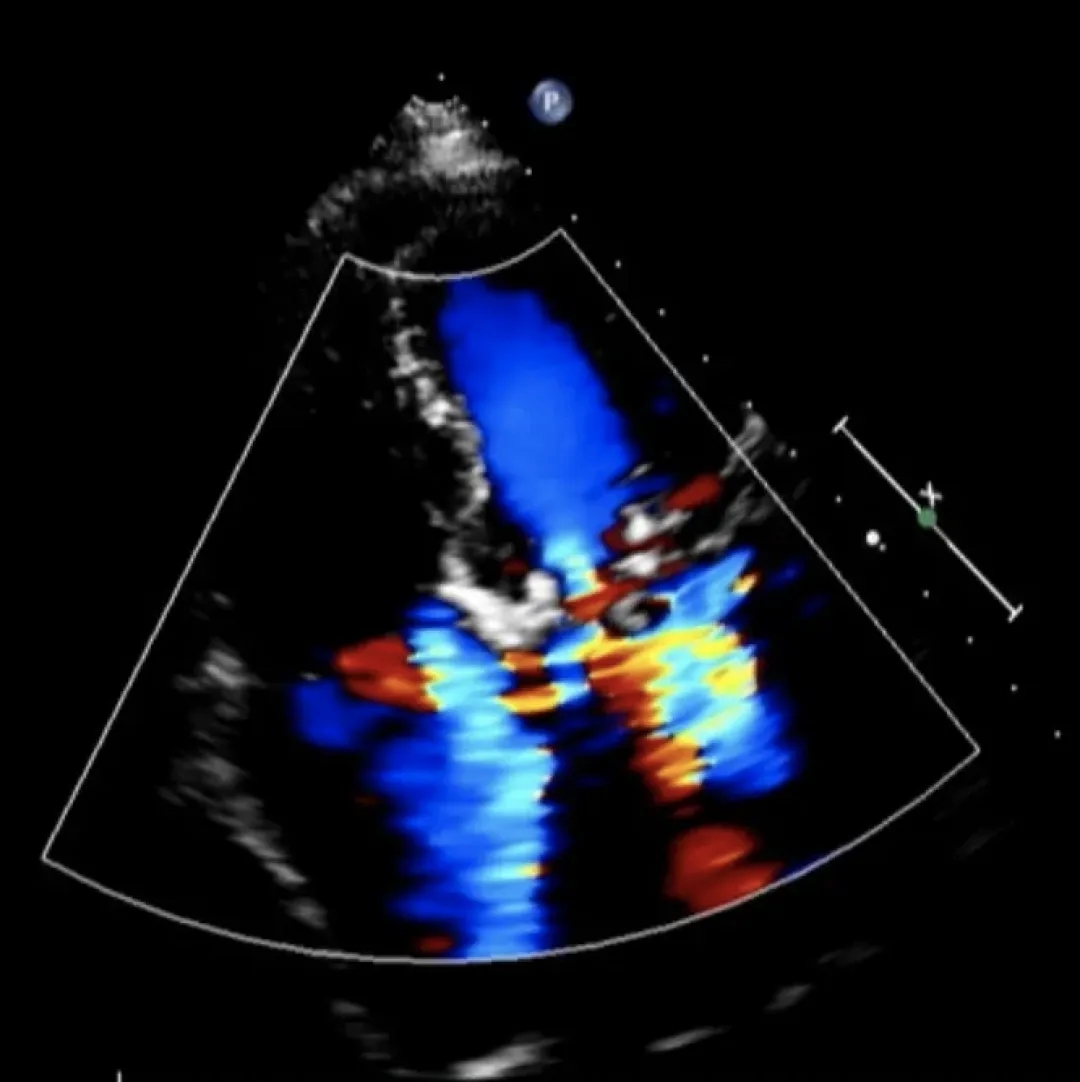

▲二尖瓣重度返流